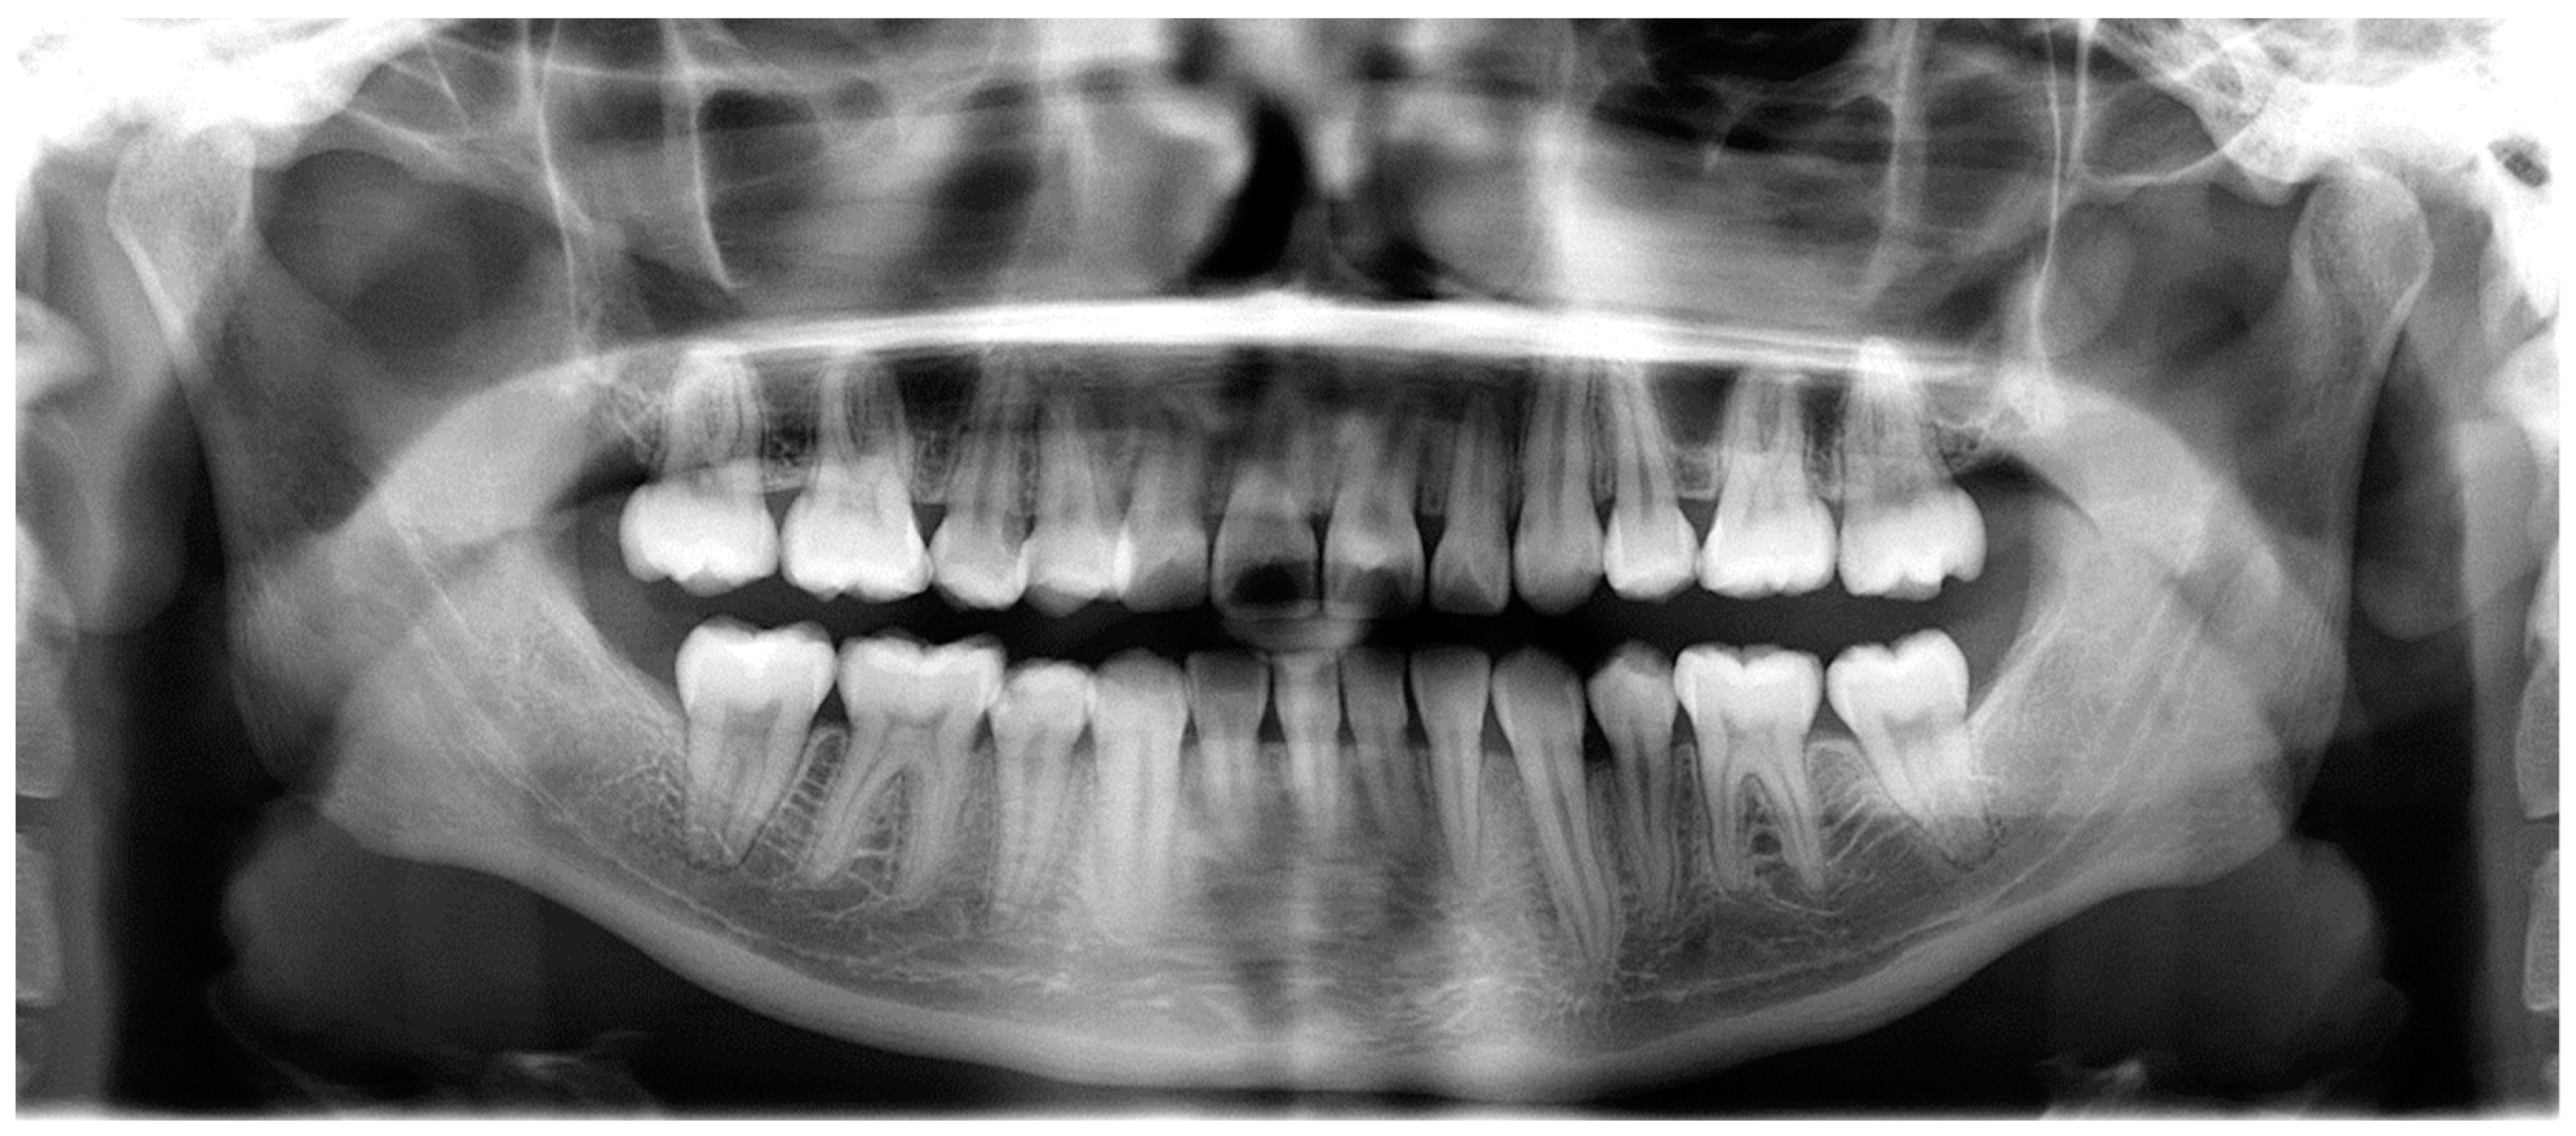

- Assessment of proposed sites of temporary anchorage device (TAD). Figure 11, Figure 12, Figure 13 and Figure 14 show correction of the Class II molar relationship using a temporary anchorage device. Figure 11 shows a pre-treatment intraoral photograph of the right side. The Class II molar relationship can be observed. Figure 12 shows coronal, sagittal and axial views, as well as a volume rendering of CBCT that was acquired in order to assess the site of the temporary anchorage device. Figure 13 shows an intraoral photograph of the right side, in which the TAD was placed mesial to the maxillary first molar, and a power chain was attached from this TAD to a hook placed distal to the lateral incisor. Figure 14 shows a post-treatment intraoral photograph showing improvement of the Class II molar relationship after removal of all orthodontic appliances.